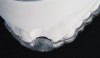

Figure 7  These images summarize the various dimensional assessments that underscore the Rules of Six guidelines, which enable simple planning for uncomplicated single-tooth dental implant therapy: Finding mesiodistal or inter-radicular (Fig 7), buccolingual (Fig 8), and inter-occlusal (Fig 9) distances of 6 mm can assure uncomplicated implant placement and restoration.

Figure 8  These images summarize the various dimensional assessments that underscore the Rules of Six guidelines, which enable simple planning for uncomplicated single-tooth dental implant therapy: Finding mesiodistal or inter-radicular (Fig 7), buccolingual (Fig 8), and inter-occlusal (Fig 9) distances of 6 mm can assure uncomplicated implant placement and restoration.

Figure 9: These images summarize the various dimensional assessments that underscore the Rules of Six guidelines, which enable simple planning for uncomplicated single-tooth dental implant therapy: Finding mesiodistal or inter-radicular (Fig 7), buccolingual (Fig 8), and inter-occlusal (Fig 9) distances of 6 mm can assure uncomplicated implant placement and restoration.